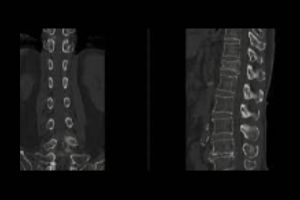

NCCT Temporal Axial and Coronal

Medifyhome offers NCCT Temporal Axial and Coronal scans, a non-contrast computed tomography (NCCT) imaging service for the temporal bone of the skull. This type of scan gives you detailed axial and coronal views of the temporal bones, which protect the inner ear structures and surrounding tissues. Recommended for patients with hearing loss, dizziness, infections, or trauma-related injuries, the NCCT Temporal scan helps to detect and diagnose fractures, infections, or abnormalities that affect balance, hearing, and facial functions. Medifyhome’s service uses advanced equipment and experienced professionals to ensure accurate imaging, so you can trust us for precise diagnostic care. With Medifyhome’s NCCT Temporal Axial and Coronal scans, you get high-quality imaging to support diagnosis and treatment plans.

What is an NCCT Temporal Axial and Coronal Scan?

An NCCT Temporal Axial and Coronal Scan is an imaging diagnostic test, where an X-ray or computed tomography (CT) scan will give a non-contrast two-dimensional view of the image of the temporal bone located inside the skull. A high-resolution scan in axial or coronal view allows health workers to assess inner ear structures efficiently. The main clinical condition diagnosed by this scanning tool is fracture, infections, and other abnormalities involving an impairment in hearing or maintaining balance. This makes the scan a very useful tool in the diagnosis and treatment of patients with otologic or neurologic disorders.